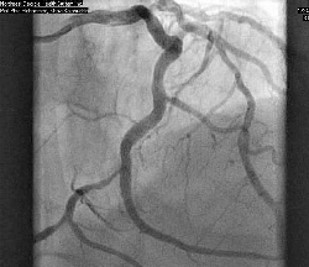

Patient was informed of these high-risk findings on CCTA with evidence of obstructive CAD and the decision was made to proceed with the gold standard left heart catheterization with coronary angiography to ensure accuracy of the obstructive lesion and intervention if the lesion was found to be obstructive. Cardiac catheterization revealed an obstructive lesion of the mid LCx with 80% calcified stenosis and he underwent successful Intravascular Ultrasound (IVUS) guided PCI of the LCx with pre and post balloon angioplasty utilizing a 3.5x22 and 3.0x15 mm overlapping Onyx frontier Drug-Eluting Stent (DES). LAD lesion angiographically appeared to be non-obstructive and medical management was elected (Figures 2-4).

Figure 3: Coronary angiography showing proximal LCx lesion.